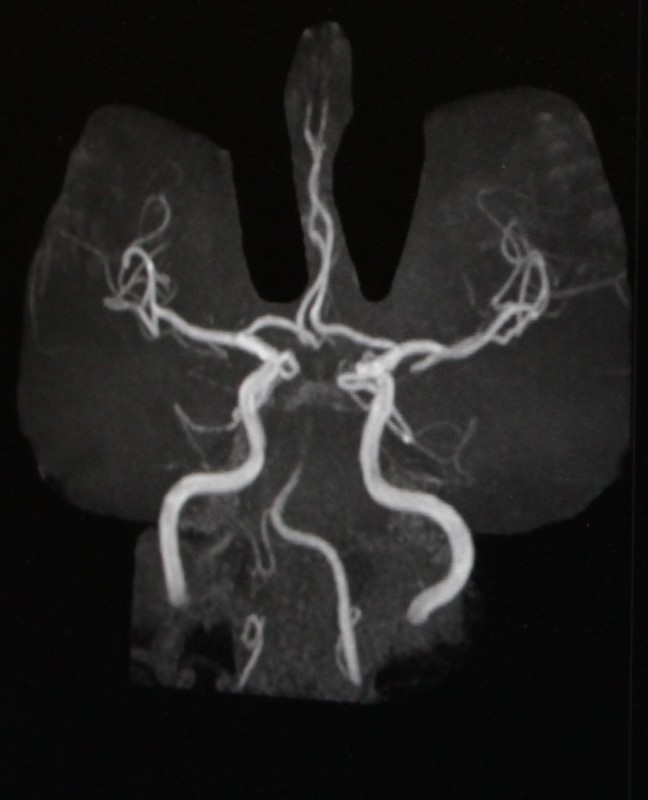

下図は実際のカテーテル治療前とカテーテル治療後の病変部の所見です。治療前には遮断されていた血流が治療後には再開通されて、レントゲンにもくっきりと血管像が写っていることがわかります。